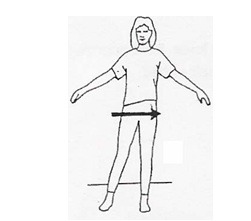

وزن را از یک پا روی پای دیگر بیاندازید. در ابتدا از سطح محکمی بگیرید. این حرکت را 10 بار تکرار کنید.